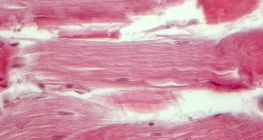

zumiranje: 400x